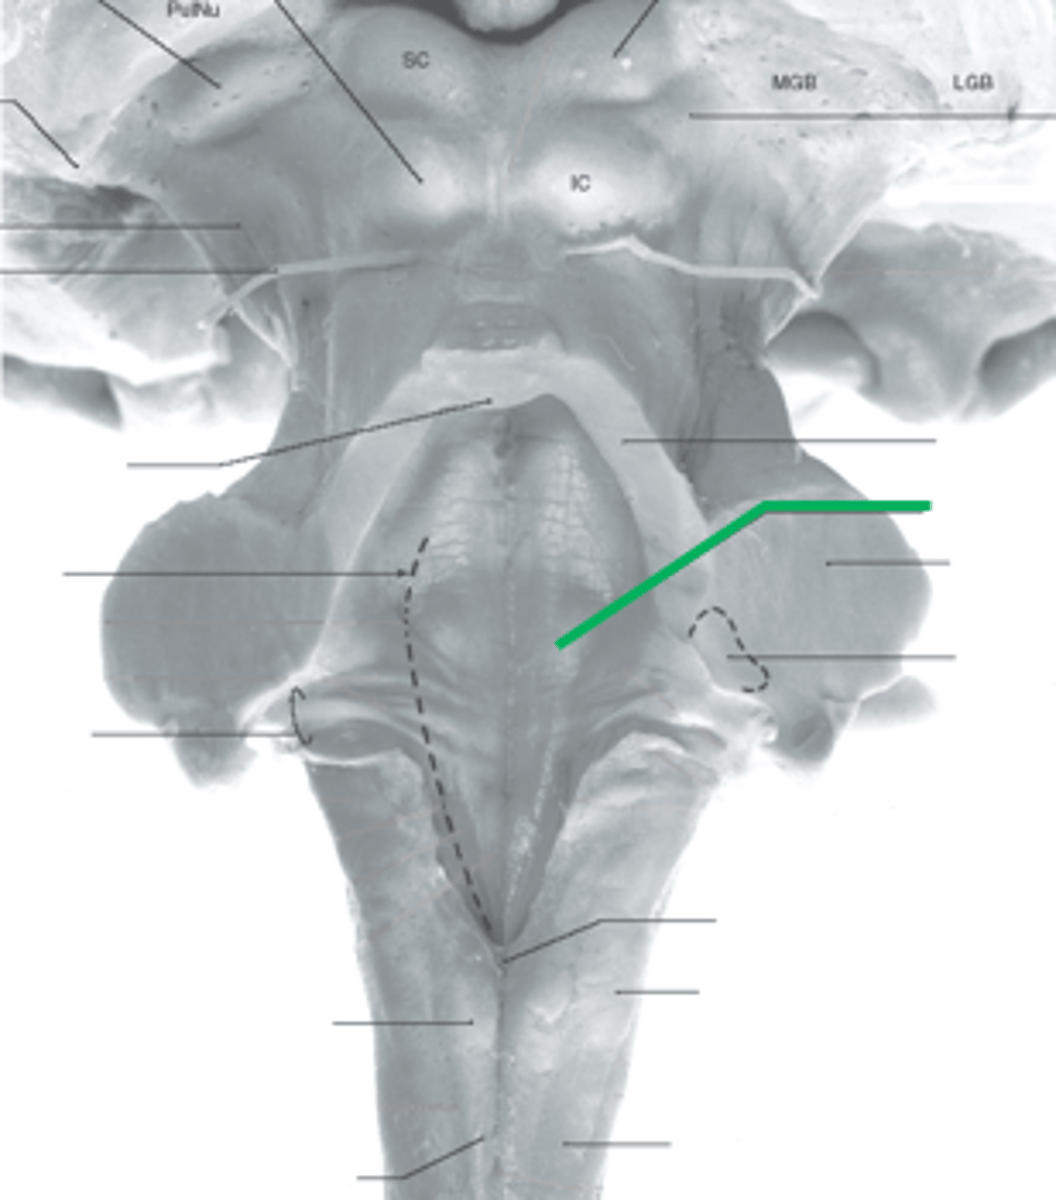

What anatomical aspect of the 4th ventricle is considered its floor?

ventral

refers to the floor of the 4th ventricle

rhomboid fossa

What forms the floor (rhomboid fossa) of the 4th ventricle?

dorsal surfaces of pons tegmentum and open medulla

inferior angle of the floor of the 4th ventricle

obex

vertical groove running in the floor of the 4th ventricle that separates it into right and left halves

dorsal median sulcus

vertical groove lateral to the dorsal median sulcus of the 4th ventricle

**same one that separated the alar and dorsal plates in the neural tube during development

sulcus limitans

refers to most of the floor of the 4th ventricle lateral to the sulcus limitans

**namesake nuclei are here

vestibular area

triangular region located in the caudal portion of the rhomboid fossa of the 4th ventricle, where the dorsal motor nucleus of CN X is

vagal trigone

Which parasympathetic nucleus is found in the vagal trigone of the 4th ventricle?

dorsal motor nucleus of X

triangular region located most medially in the caudal portion of the rhomboid fossa of the 4th ventricle, where the CN XII nucleus is

hypoglossal trigone

part of the 4th ventricle superior to the vagal and hypoglossal trigones (still medial to the sulcus limitans)

medial eminence

small bump located in the caudal portion of the medial eminence which forms from the motor fibers of CN VII as they wind around the underlying CN VI nucleus

facial colliculus

pigmented area that looks blue near the superior aspect of the sulcus limitans; cluster of noradrenergic cells

locus ceruleus

fibers that run horizontally in the central region of the rhomboid fossa of the 4th ventricle

stria medullares

area that helps to make the walls of the obex and is thought to be the "vomit trigger"

area postrema

What anatomical aspect of the 4th ventricle is considered its roof?

dorsal

What forms the superior portion of the roof of the 4th ventricle? (A)

superior cerebellar peduncles

inverted V shaped interval between the superior cerebellar peduncles that is filled by a thin layer of white matter

superior medullary velum

lower portion of the roof of the 4th ventricle formed by a thin layer of pia mater and ependymal cells

inferior medullary velum

structure attached to the ventral surface of the inferior medullary velum in the 4th ventricle that helps form CSF

choroid plexus

opening in the caudal aspect of the inferior medullary velum that allows CSF from the 4th ventricle to flow into the cisterna magna of the subarachnoid space

foramen of Magendie (or median aperture)

What mostly forms the lateral walls of the 4th ventricle?

inferior cerebellar peduncles and choroid plexus

openings in the 4th ventricle that allows CSF to flow from the 4th ventricle into the pontine cistern of the subarachnoid space

foramen of von Luschka (or lateral apertures)

floor of 4th ventricle

rhomboid fossa

sulcus limitans

floor of 4th ventricle lateral to sulcus limitans

vestibular area

vasal trigone

hypoglossal trigone

medial eminence

small bump in caudal portion of medial eminence

facial colliculus

stria medullares

A

superior cerebellar peduncles

superior medullary velum

inferior medullary velum